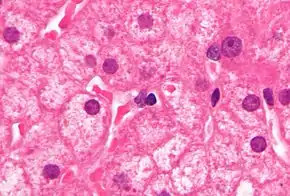

PCR tests have been developed to detect and measure the amount of HBV DNA, called the viral load, in clinical specimens. These tests are used to assess a person's infection status and to monitor treatment.[62] Individuals with high viral loads, characteristically have ground glass hepatocytes on biopsy.